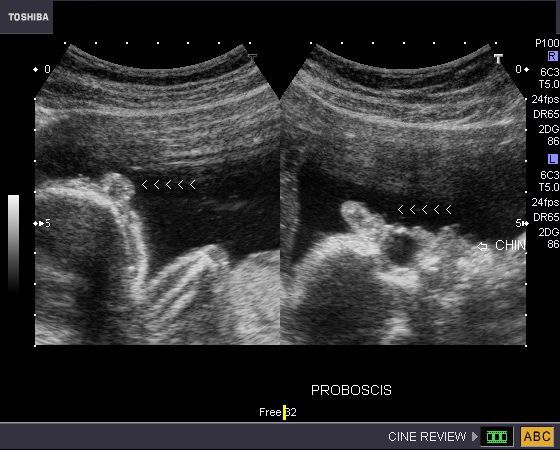

Hypotelorism, proboscis, with Holoprosencephaly and overriding of aorta in fetus

This late 2nd trimester fetus underwent routine obstetric sonography. Ultrasound imaging showed hypotelorism (both orbits are very close to each other), a small fleshy projection above the eyes in the region of the forehead (proboscis), holoprosencephaly (single fused monoventricle) and cardiac anomaly (over riding of aorta). The presence of hypotelorism and proboscis is called ethmocephaly. Holoprosencephaly, especially the severe form, (alobar) is often associated with multiple facial anomalies of this nature. The prognosis, in this fetus is very bleak. Trisomy-13 and Trisomy-18 are the common chromosomal disorders found in such cases. Ultrasound images are courtesy of Dr. Durr-e- Sabih, Pakistan. These images were taken using a Toshiba Nemio-30 Ultrasound system. (OR= Orbits)